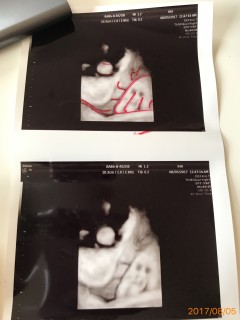

妊娠36週5日 36w5d の超音波 エコー 写真